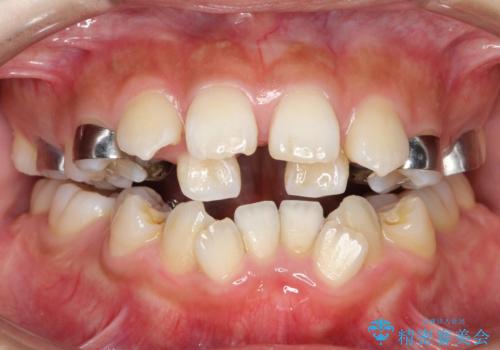

人生が変わる 困難を極める咬合状態に歯列矯正単独で挑戦する

- 上顎の骨格性拡大+両側第1小臼歯抜歯 によりスペースを獲得、フルリンガルによるワイヤー矯正を計画した。

骨格的要因を背景にもつ不正咬合のため、歯列矯正単独での改善は困難と判断しましたが、患者さんとの相談の結果、歯列矯正単独で可能なところまで一緒に頑張りましょうということで、治療をすすめました。

シビアな叢生や開咬も改善することができ、想像以上の改善に時間をかけた甲斐があったと満足していただけました。